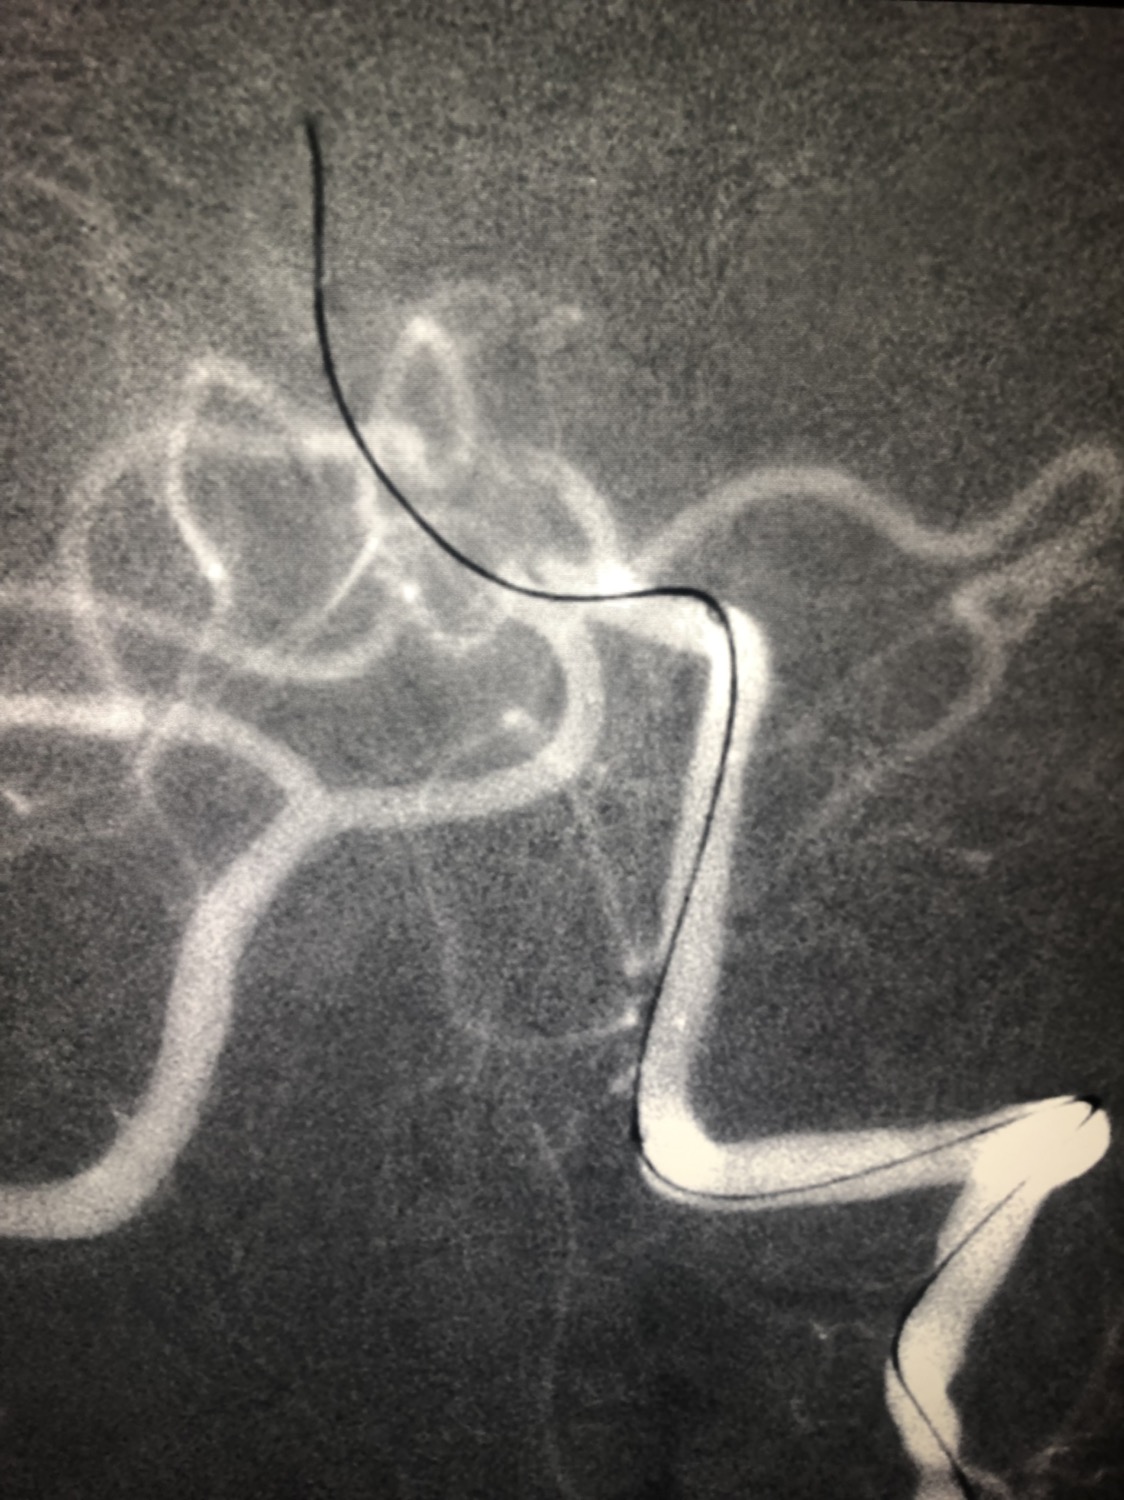

急诊二。zde,f53y。

意识模糊进行性加重8h,基底动脉闭塞,reco取栓再通,貌似动脉硬化,实际血管光滑。造影➕取栓8min。今日团队配合紧密,不到三小时全麻造影取栓带苏醒完成两台取栓。团队棒棒的!南阳市中心医院神经内科脑血管病介入团队